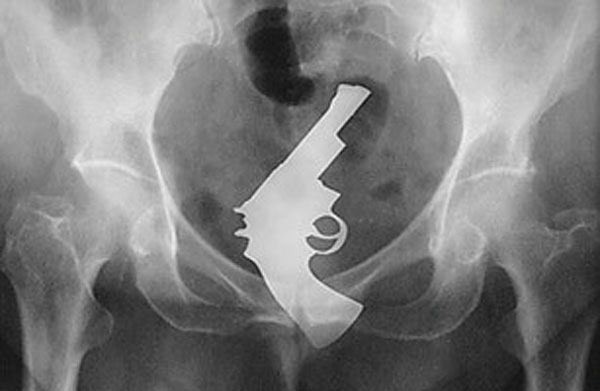

Одним из лидеров недели в Twitter стал хештег #WeirdThingsToPutUpYourAss (Странные штуки, которые суют в задницу). Проктологи со всего мира поделились рентгеновскими снимками содержимого анусов своих пациентов. Выяснилось, что огурец - еще не самое удивительно, что можно обнаружить там, где не светит солнце.